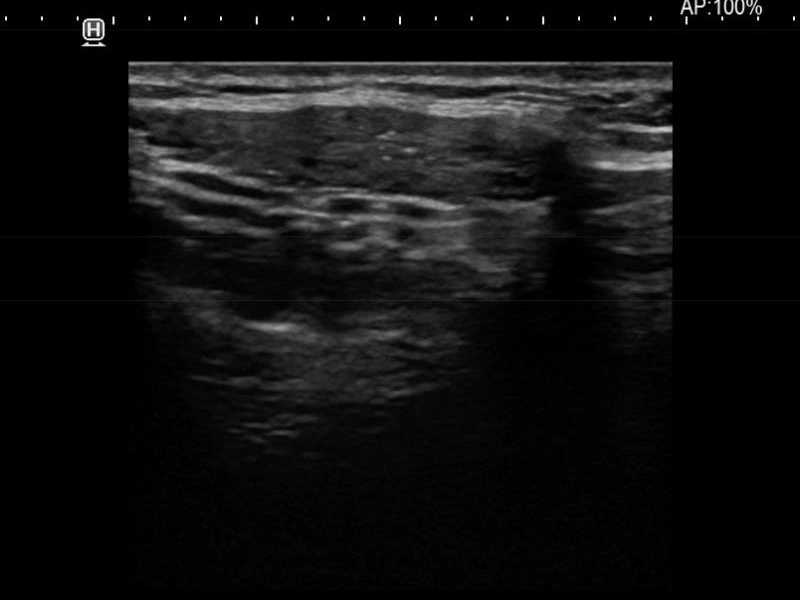

Ultrasonography. The thyroid was moderately hypoechoic and presented with numerous more and less hypoechoic discrete lesions. The largest of the latter was in the lower ventromedial part of the left lobe and had cystic areas and intranodular echogenic figures. The latter included typical comet tail artifacts, back wall cystic figures and some ambiguous small bright granules. The lesion showed both perinodular and intranodular vascularity. Compared with the former examination the nodule increased by 22% in volume. This difference is within the intraobserver variation.

Comment. Based on the presence of typical comet-tail artifacts, the questionable punctate echogenic granules are worth considering also colloid crystals.